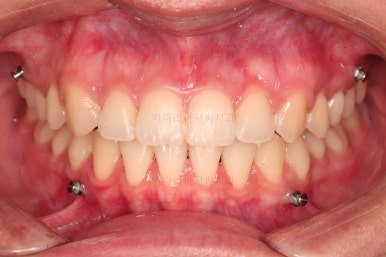

아랫니 틈은 거의 없어졌네요.

대신 여러 교합적인 이유로 아랫니를 좀 더 앞으로 당겨주긴 해야 합니다.

이제 마무리를 해봅니다.

교합 양호하고 치아 사이 틈새도 잘 모아졌습니다.

이제 부산치아교정 전후 비교를 해볼게요.

틈새가 예쁘게 모아졌고요.

교합도 좋아졌고, 앞니도 가지런해졌네요.